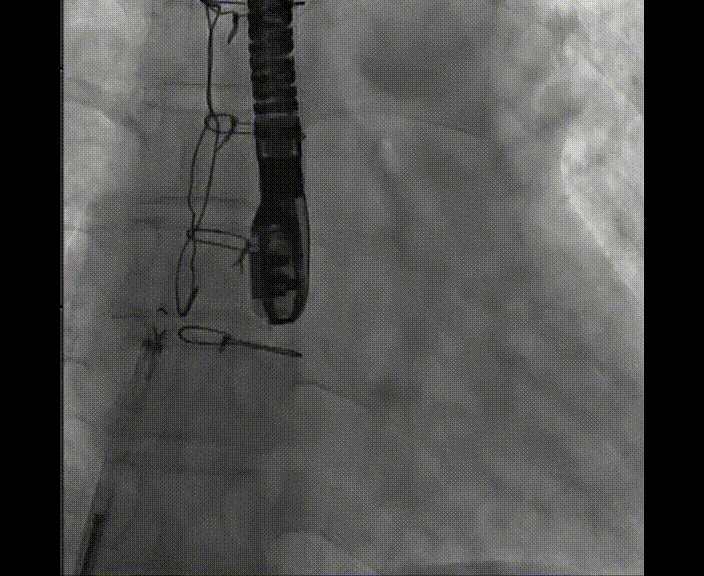

術中首先在局麻下穿刺股動脈、股靜脈,完成心導管檢查評估后轉為全麻,在食道超聲引導下穿刺房間隔,穿刺成功后將加硬導絲送入左上肺靜脈建立軌道,根據患者病情行球囊預擴張后植入6mm孔徑房間隔造孔支架,經透視及食道超聲評估支架左右盤展開良好,夾持于房間隔兩側,固定穩定、位置良好,食道彩超顯示房水平右向左為主分流,分流孔直徑符合預期大小,心導管檢查評估達到預期效果,釋放造孔支架。術后12h患者下床活動,恢復順利,擬于近日完善術后評估后出院。